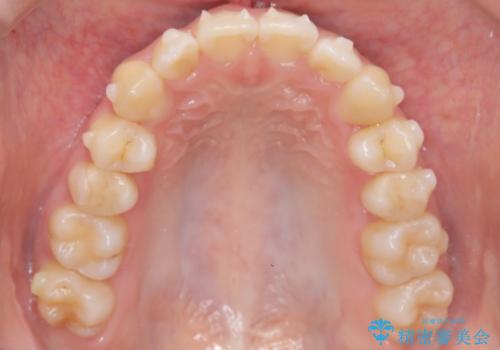

- 右上の前歯(2番)が下の歯より内側に入っている反対咬合を主訴にご来院されました。精密な検査の結果、この反対咬合を解消するためには、右上の歯列に前歯を出すためのスペースを確保する必要があると判明しました。患者様のご希望に合わせ、透明で目立たないインビザライン(マウスピース矯正)による治療計画を立案。奥歯全体を奥へ動かす遠心移動でスペースを作り、反対咬合を解消することを目指します。

今回の矯正治療では、透明なマウスピース型の装置インビザラインを使用しました。治療は、緻密なデジタル計画に基づき、奥歯から順に歯列全体を後方へ移動させる遠心移動を実施し、前歯を前に出すためのスペースを確保しました。このスペースを利用して、内側に入り込んでいた右上2番をスムーズに前方に誘導し、正常な咬み合わせへと改善。目立たないインビザラインで、機能的な咬み合わせと美しい前歯の並びを獲得していただけました。